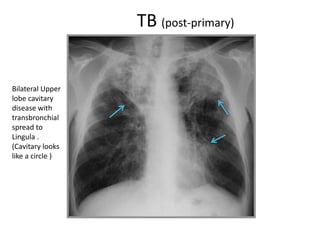

Bilateral Upper

lobe cavitary

disease with

transbronchial

spread to

Lingula .

(Cavitary looks

like a circle )

• Post-primary TB (TB Reactivation)

-Calcification is usually rarer than in 1ry.

-Limited mainly to the apical & posterior segments of upper lobes & superior

segment of lower lobe.

-Bilateral upper lobe disease is very common.

-Cavitation may result ; Cavity is usually thin walled ,smooth or inner margin with

no air-fluid level.

-Transbronchial spread might occur from one upper lobe to opposite one.